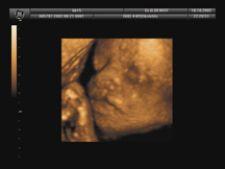

A similar phenomenon characterized the early adoption of 3D ultrasound. Initially, a common perception of 3D ultrasound is that it is of greater aesthetic than clinical value. One can easily gauge the appeal of the images obtainable of fetuses through obstetric imaging with 3D ultrasound. The fact that 3D ultrasound has been the object of such massive advertising efforts in general-public literature, in particular for its fetal imaging applications, corroborates the notion that the early demand was driven primarily by patients, and not by physicians whose evaluation relies strictly upon diagnostic value.

Since then, however, with a broadening of its clinical applications and its increasing sophistication, such as the ability to perform 4D scans, and with positive prospects in the key area of cardiac imaging, 3D ultrasound has been gaining more widespread clinical acceptance. With 3D ultrasound now available in convenient laptop and hand-held platforms, researchers predict that doctors will eventually have ultrasound stethoscopes to perform quick routine examinations. Primary physicians would use ultrasound to see the heart and check other vital signs; obstetricians to analyze a baby’s heartbeat, and first responders could use in emergency situations.